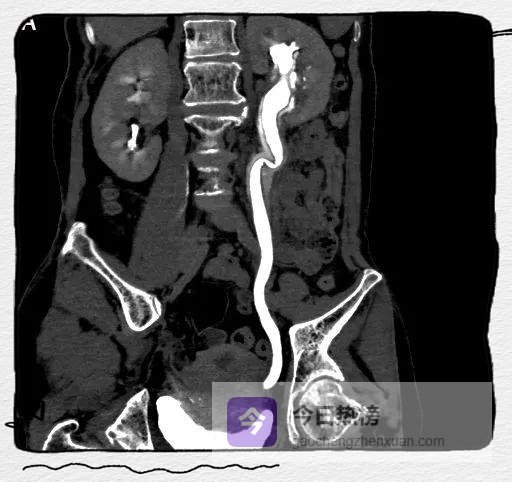

图4A

图4A-C

左侧肾盂及输尿管上段呈“双环及双腔样”改变,考虑夹层形成;三维重建可清楚的观察到撕裂肾盂及输尿管的真假腔并显示撕裂范围。